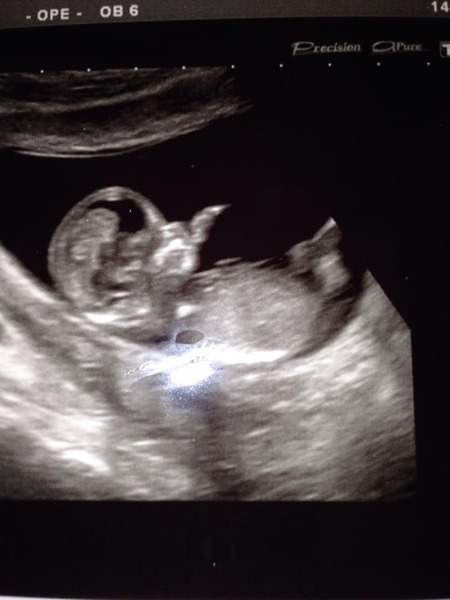

My little one. (Flash on camera gives white dot in middle)